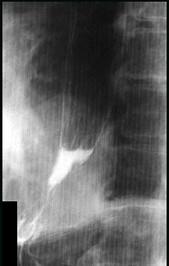

问题 女性,65岁,进行性吞咽困难半年,消瘦,钡餐检查如图,最佳的诊断是 ( )

选项 A.贲门失弛缓症 B.食管静脉曲张 C.食管鳞状(上皮)细胞癌 D.贲门癌 E.反流性食管炎

答案 C